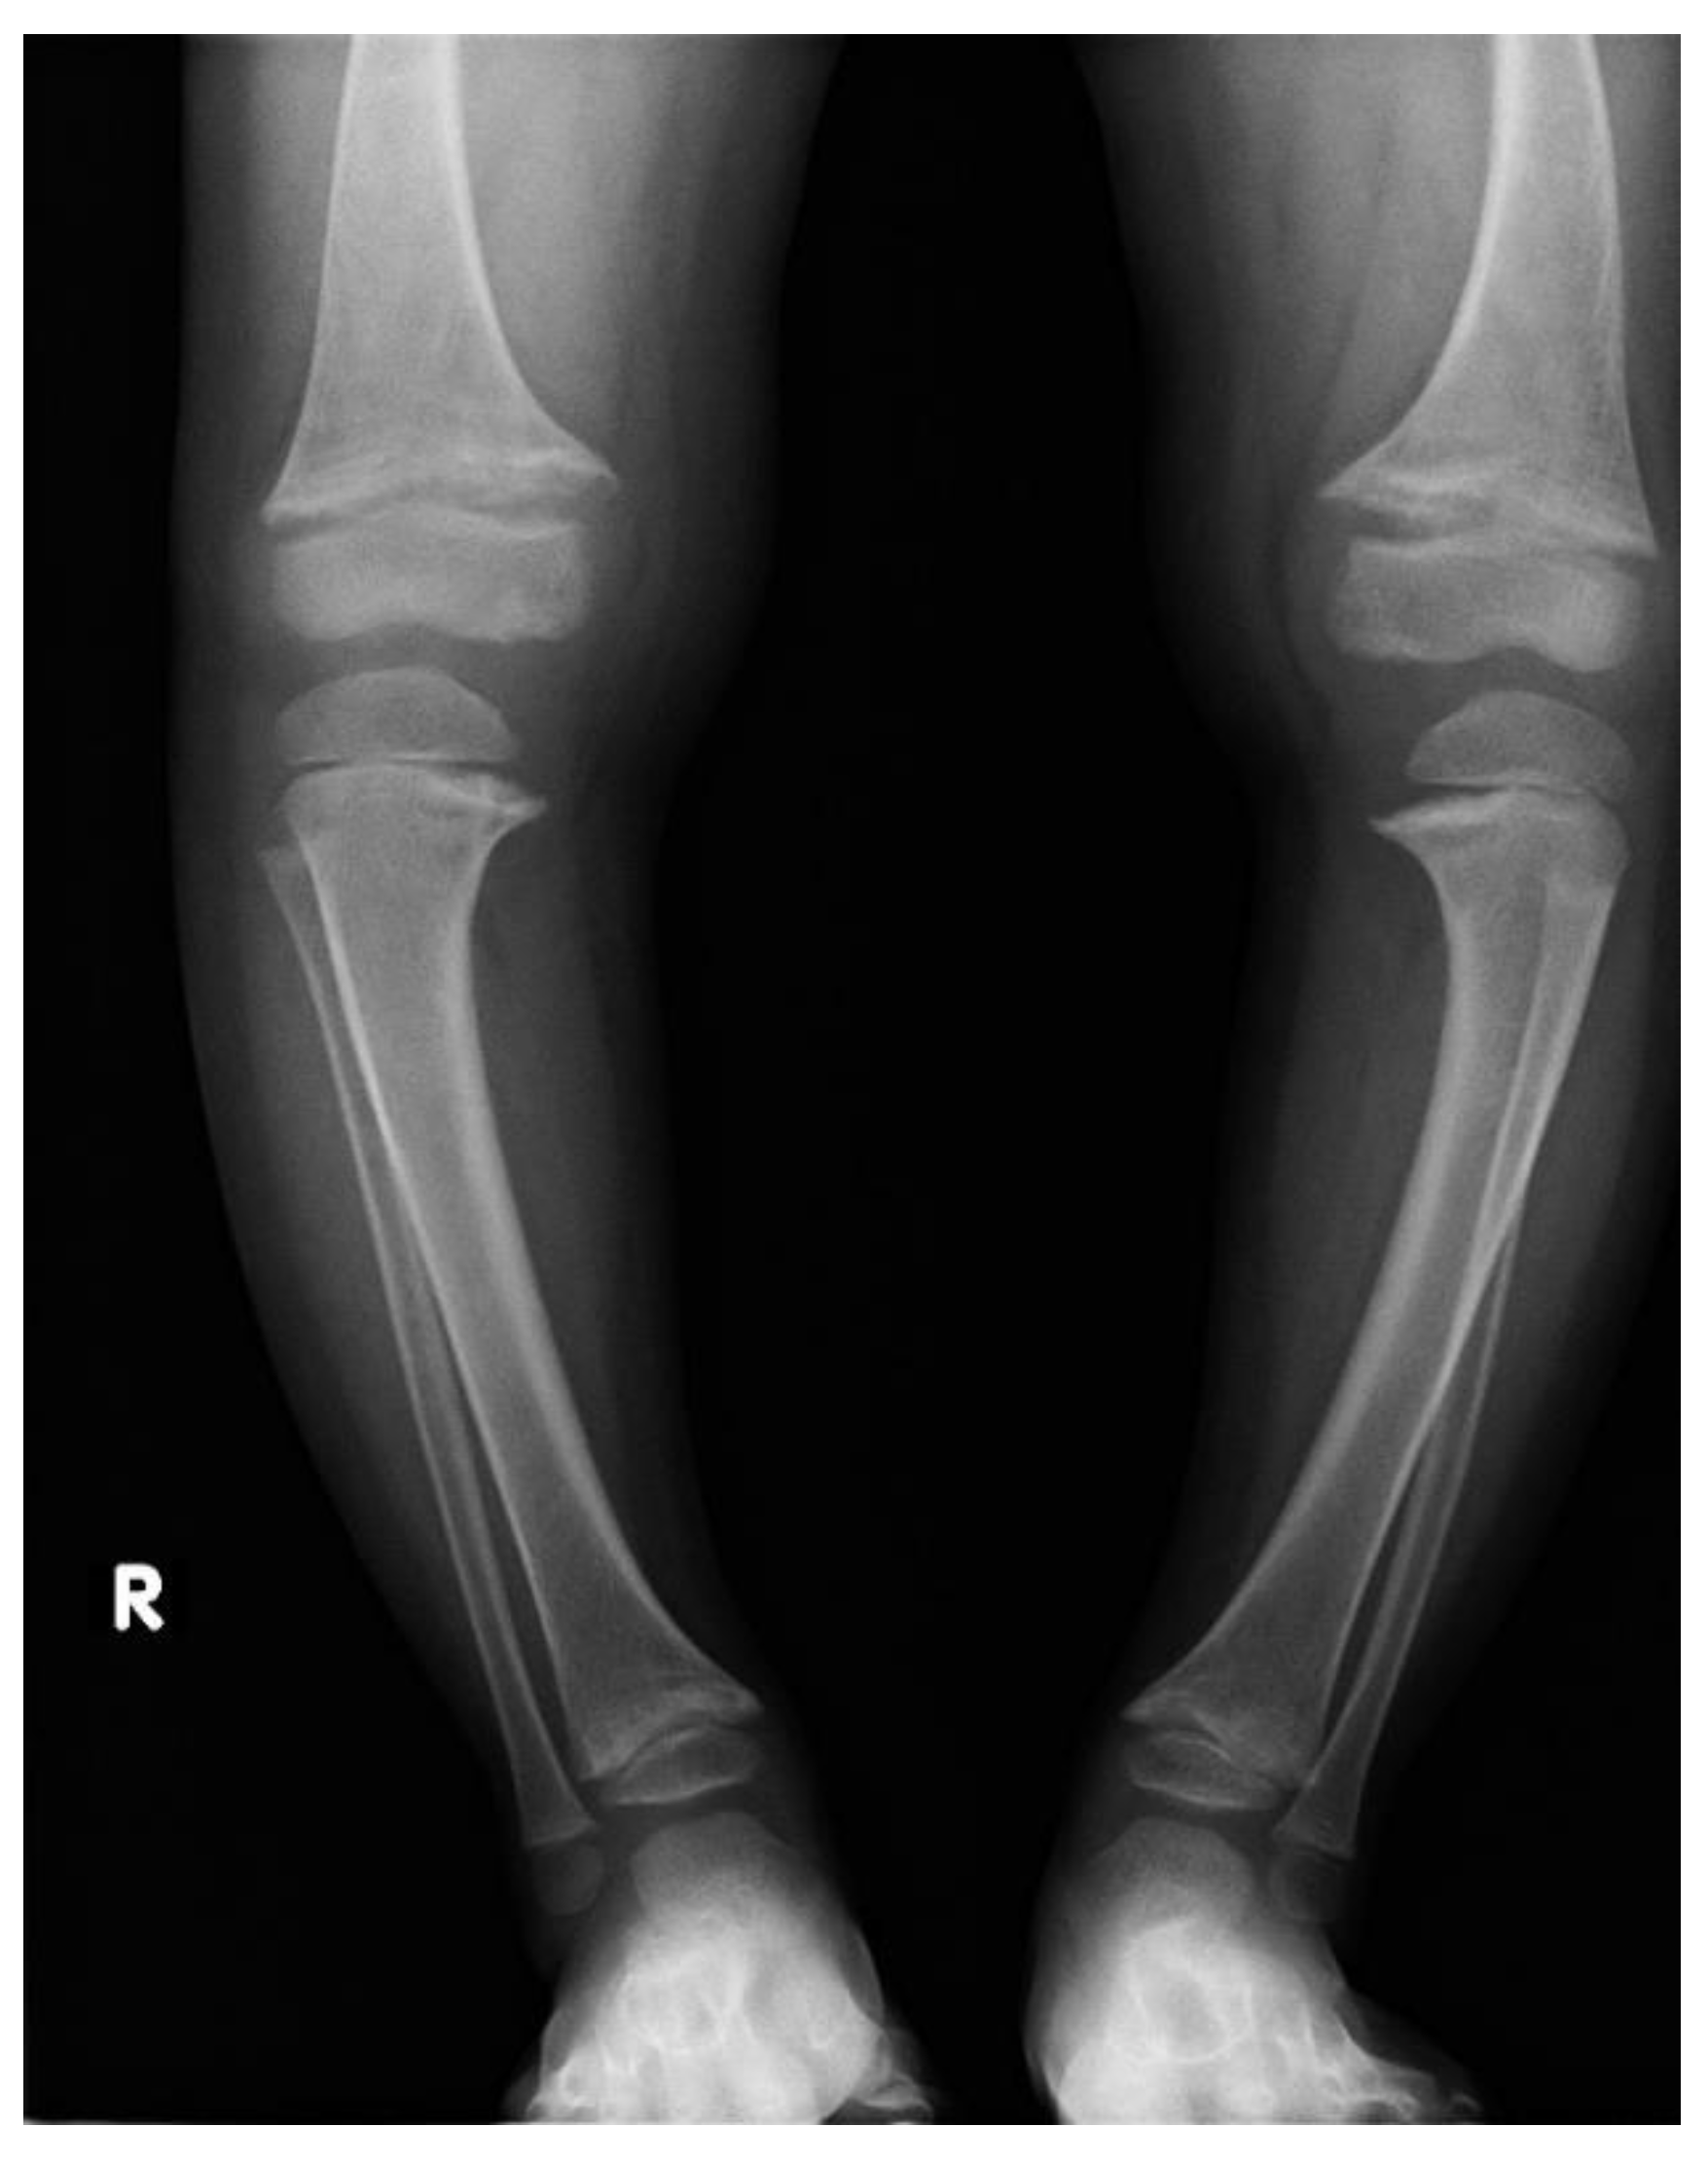

Irrespectively of inheritance pattern, all congenital forms of hypophosphatemic rickets present similar phenotypes including short height along with age and typical changes in the skeleton. Characteristic bone symptoms of hypophosphatemic rickets include varus deformity of the lower extremities, frequently severe, which appears after the child starts walking—usually in the 2nd year of life—that also progresses with age and may lead to gait disturbances and require surgical correction [6,7] (Figure 1 and Figure 2).

Figure 1.

A 15-year-old girl diagnosed with hypophosphatemic rickets; significant varus deformity of the lower extremities is visible in spite of surgical and medical treatment.